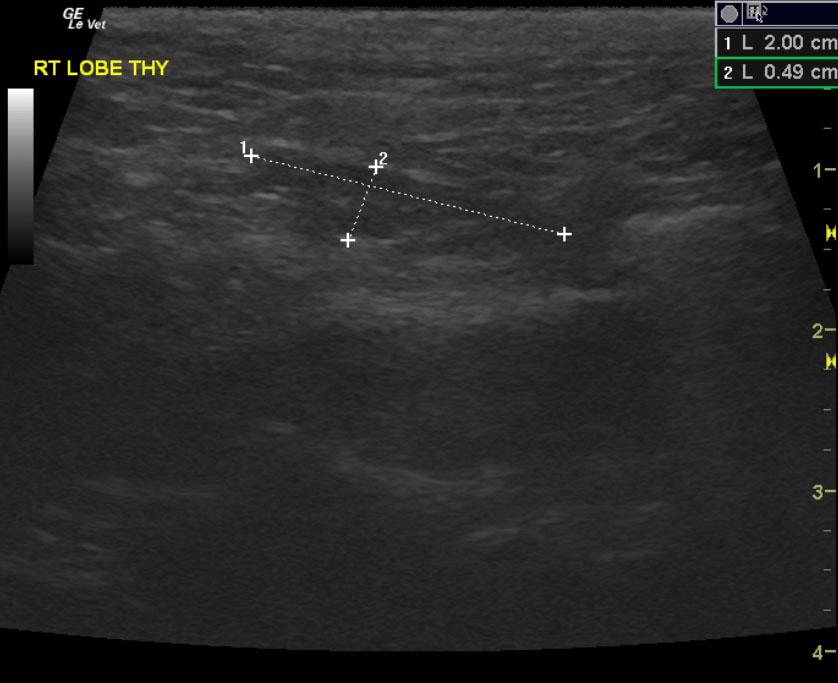

A 9-year-old male neutered Plotthound dog was presented for evaluation of polyuria, polydypsia, and occasional loose stool. Abnormalities on CBC and serum biochemistry included mild anemia, mild leukopenia, mildly increased ionized calcium, and mild azotemia. T4 was within reference range at 4.4.